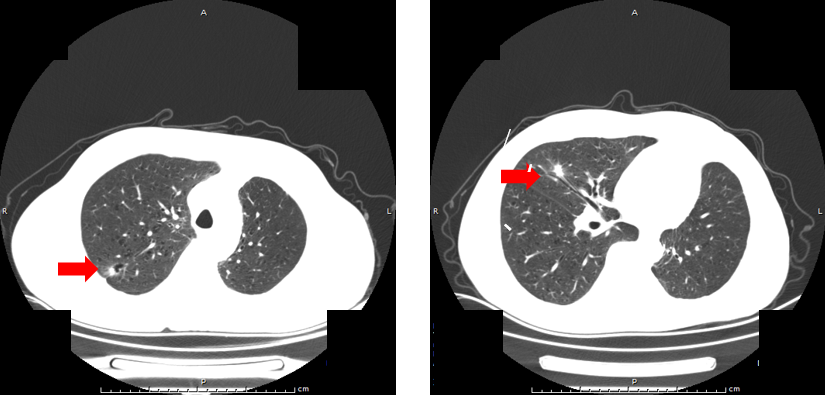

第二阶段:复发及局部治疗(2022-07至2023-01)

首次复发:2022年7月,放疗后1年复查发现右肺结节,当地医院予以奥希替尼靶向治疗(基于术后EGFR 19del突变)。

局部进展:2022-11复查示右肺结节较前稍增大。2022-11-15日至2022-11-27行胸部SBRT,GTV1及GTV2处方剂量50Gy/5次。

SBRT后评估:2023年1月复查,右肺结节较前缩小。